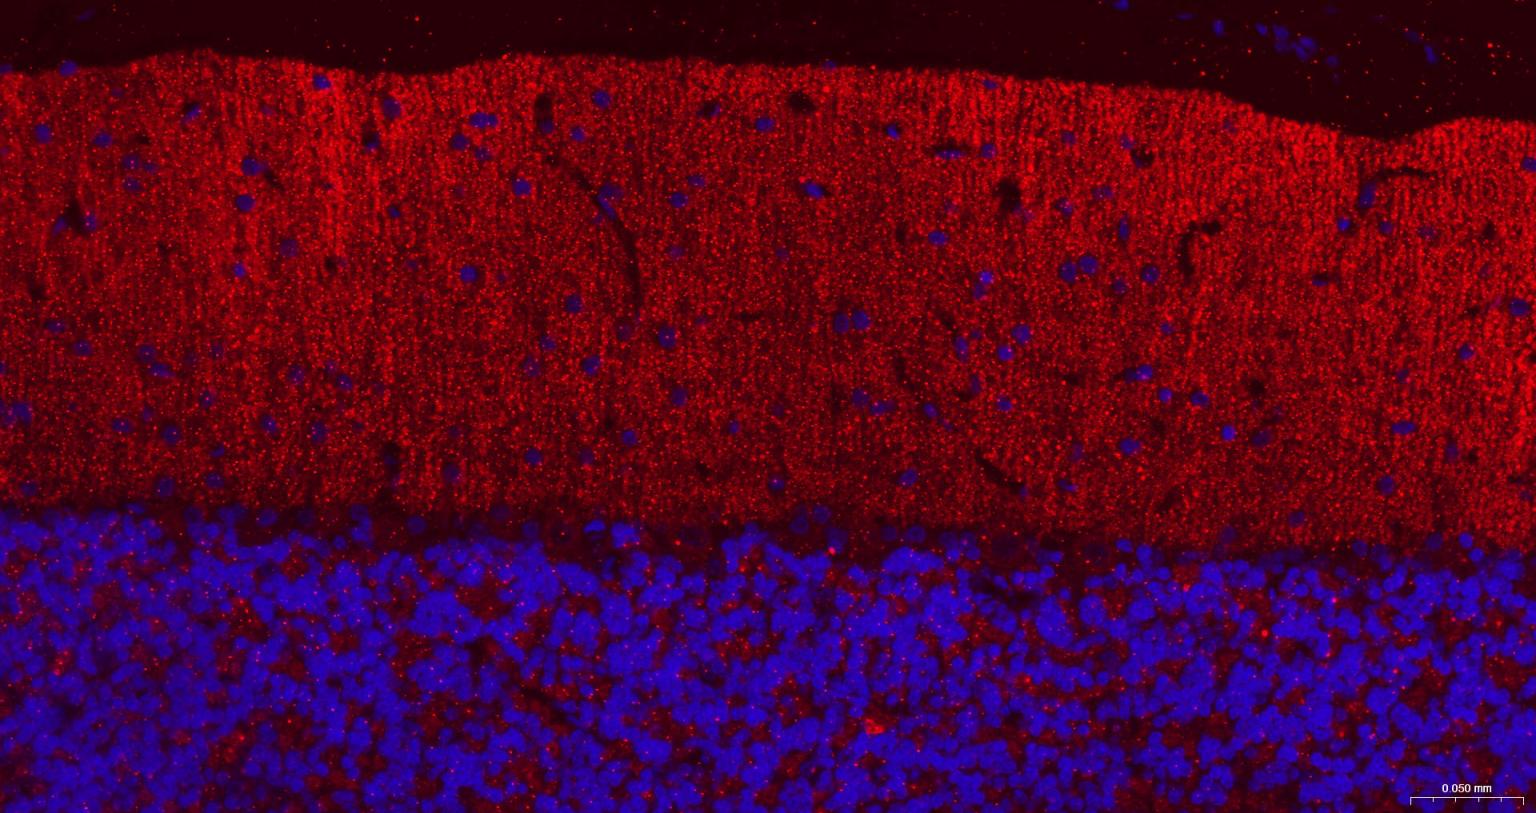

IHC-PHuman, Mouse, Rat1:50-200

IHC-FHuman, Mouse, Rat1:50-200

组织特异性

Highly expressed in brain, especially in cerebral cortex, thalamus, hippocampus, frontal, occipital and temporal lobe, occipital pole and cerebellum, followed by corpus callosum, caudate nucleus, spinal cord, amygdala and medulla. Weakly expressed in heart, testis and skeletal muscle.